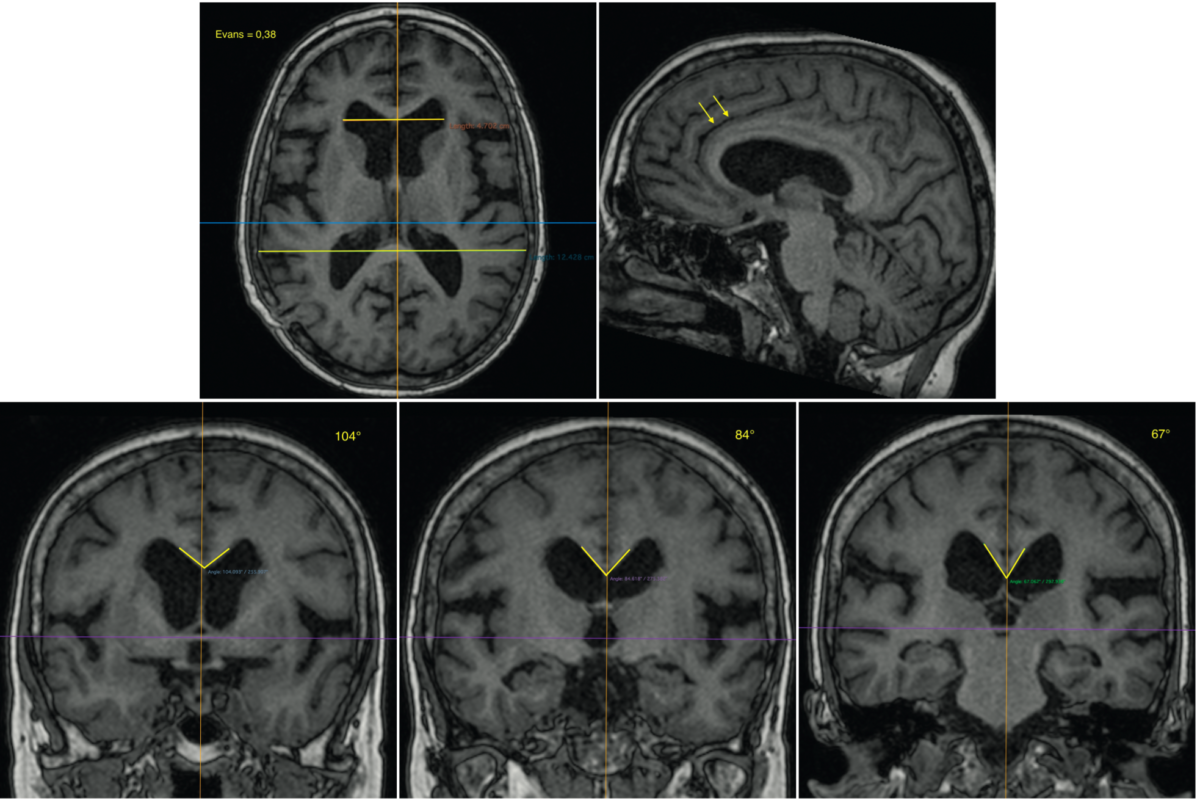

Source: bocinafji.pages.dev PPT Hydrocéphalie a pression normale PowerPoint Presentation, free download ID5612461 , L'hydrocéphalie à pression normale (HPN) a été décrite pour la première fois en 1965 par Adams et Hakim Normal pressure hydrocephalus remains a controversial entity with often ambiguous imaging findings

Source: terciartzsg.pages.dev Hydrocéphalie à pression normale une mise à jour Aerzteverlag medinfo AG , On imaging, it can be characterized both on CT and MRI by enlarged lateral and third ventricles out of proportion. L'incidence de l'hydrocéphalie à pression normale est de 5,5 personnes sur 100 000 par an

Source: scaleappnzx.pages.dev Hydrocéphalie à pression normale causes, symptômes, diagnostic et traitement esculape , Causes Dans la majorité des cas, la cause de l'hydrocéphalie à pression normale est inconnue Normal pressure hydrocephalus remains a controversial entity with often ambiguous imaging findings